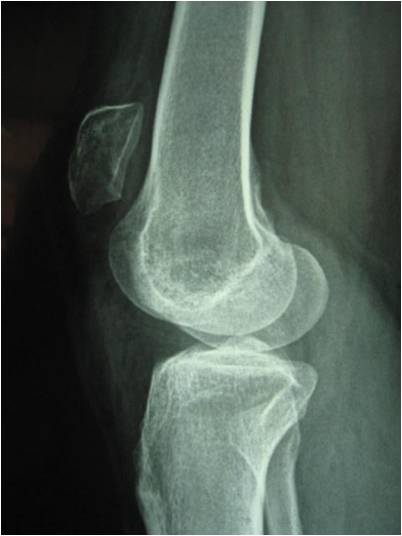

![]() Hình ảnh Xquang xương bánh chè di lệch lên cao. |